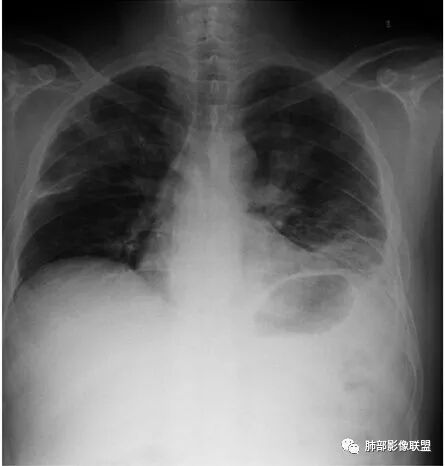

南边:患者男,44岁,以“发热1周伴咳嗽、咳痰3天” 入院。现 病 史:患者入院前1周无诱因出现寒战、发热,体温最高410C,伴肌肉酸痛、恶心、呕吐,就诊于我院, 血常规示白细胞及中性分类增高,予头孢呋辛静点1天,并口服抗生素等药物治疗。患者仍有发热,入院前3天出现咳嗽、咳暗红色血痰,伴左侧胸痛,咳嗽时加重,查胸片后收入我科。初学者:就是脓肿的话,也是坏死。然后肉芽肿边缘的壁;早期的话,它不会形成那种中央坏死壁强化的这种典型表现,但是它的特点是它很快会变化,所以有的时候不是很确定的时候,可以看那个随访。有没有高热,一般会这样判断是不是囊肿。但这个人因为肺部本身有病变,所以说,肝内的这个病变就没有办法鉴别了,那可以看一下他随访有没有变化,这个可以判断囊肿,就是从CT上它的这个壁,有的时候不是很好看,尤其是他脓肿,它形成的话,它有几个期。期不一样,它的壁的厚度、中间的坏死都不一样,所以有的时候它并不是特别的均匀,一般囊肿的话呢,我们会觉得它的分界跟周围的分解和非常的清楚,因为囊肿它是真壁。

南边:胸膜下,类圆形,边界清,内有坏死,典型的反晕征,支气管壁增厚不明显,支持血道来源脓毒栓子所致梗死、感染

血道来源没问题

左下叶大片类似病灶